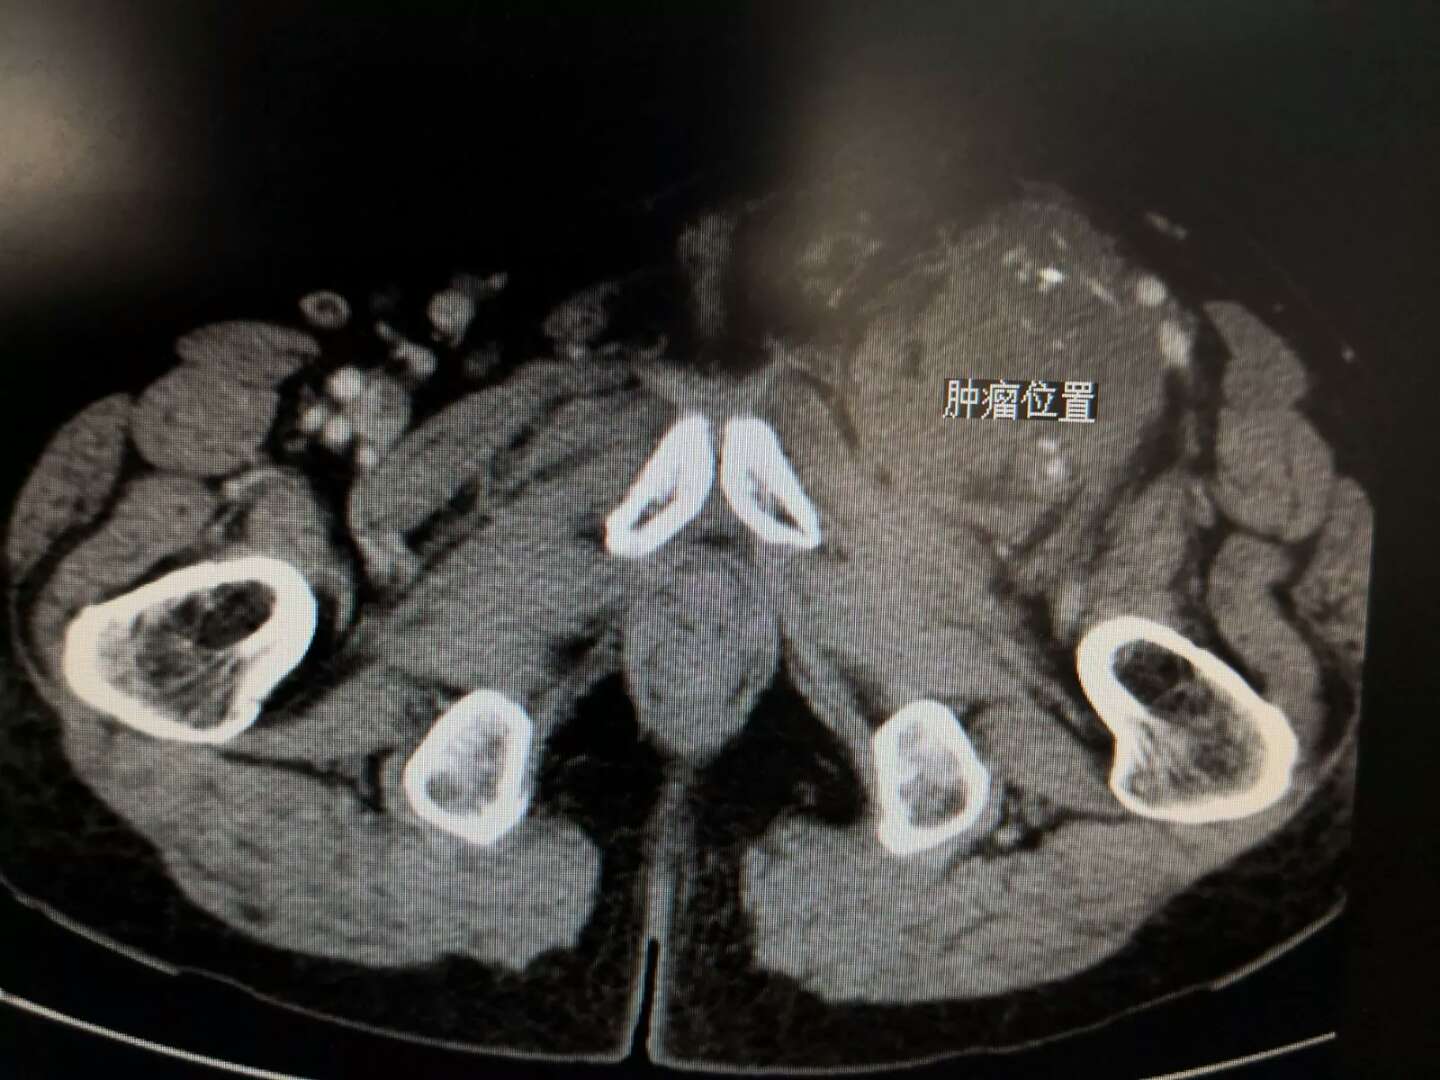

原来1年前,该患者在当地医院行手术治疗,术后病理为恶性外周神经鞘膜瘤。患者入院时查体显示:左下肢高度肿胀,左侧腹股沟区可扪及一直径约8.0cm的质硬肿物,边界不清,活动度差,足背动脉搏动可,考虑软组织肉瘤侵及重要血管导致静脉回流障碍。我院普外三科延学军主任医师团队接诊后对患者病情经过反复讨论、评估,认为二次手术难度大,治疗比较棘手,实施截肢手术患者难以接受,但放弃手术,患者病情会很快恶化。经过缜密充分的术前准备,患者于近日成功实施了血管重建联合肢体软组织肉瘤及受累大血管切除术。

为降低软组织肉瘤的复发率,手术切除在“正常组织内”进行,切除肿瘤、假包膜及周围一定范围的正常组织,尽量避免暴露肿瘤组织。手术难度在于血管为肉瘤所包裹而无法分离,术前拟行动静脉血管同时置换,幸运的是术中该患者股动脉自肿瘤成功剥离,但股静脉已闭塞,腔内癌栓形成,决定将肿瘤内的股静脉连同肿瘤一并切除。手术完整切除肿瘤,并切除股静脉长度约13㎝,股静脉血流通过人工血管置换建立,保存了患者肢体功能。